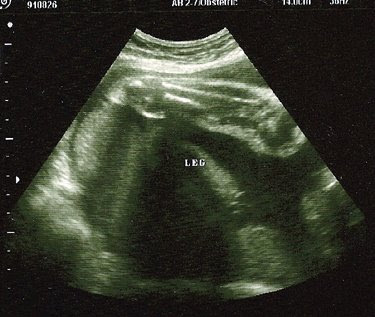

And then it swiftly kicked that ultrasound wand right off my belly.

Bones of one leg (knee joint in the top left hand corner). The leg length and activity have gotten comments at all the later ultrasounds.